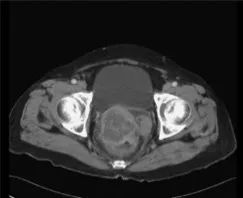

背景:腹腔内硬纤维瘤(DTs)可以和胃肠道间质瘤(GISTs)的复发或进展很相似。对该病的鉴别诊断针对避免不必要或不适当的治疗很重要。病例总结:8例患者均经历了胃肠道间质瘤手术切除,手术切除后诊断腹腔内硬纤维瘤的中位时间为1.8年。腹腔内硬纤维瘤发生部位均在GIST手术部位周围腹膜。以下临床怀疑加上放射学检查结果可有助于诊断腹腔内DTs:(1)在GIST手术部位周围的腹膜出现新的单一病变;(2)在其他病变用伊马替尼控制好的情况下,该病变不受控制;(3)CT显示有明确的卵圆形病变,伴有延迟或轻度强化,无坏死、出血和囊性改变;(4)PET显示轻度或无高代谢活性的病变,与最初的GIST高活性病变相反。除一个不可切除外,所有DTs均手术切除,其中只有一个DTs在另一个腹膜部位复发,也被手术切除。结论:GIST患者新的单一病变应与腹腔内DT进行鉴别诊断。

这是一篇很有意思的病例总结的文章。8例看似胃肠间质瘤术后复发的病例,但Tki药物治疗效果不佳,手术切除活检证实为腹腔内硬纤维瘤(DTs)。我们在临床上经常可以看到,随着GIST患者存活率的延长,这些患者确实可以发生其他原发性恶性肿瘤。尽管GIST与其他恶性肿瘤之间的关联尚不清楚,但各种实体瘤和血液学恶性肿瘤与GIST同时或异时发现的文献已有很多报道。如文章所言,GIST患者发生DT的风险评估明显高于普通人群。大多数DT病例(75%)发生在GIST后,表现类似于GIST的复发或进展,给我们临床医生带来很大的迷惑。如何区分是GIST复发进展,还是DTs?这篇文章给我们提供了很好的经验:(1)在GIST手术部位周围的腹膜出现新的单一病变;(2)在其他病变用伊马替尼控制好的情况下,该病变不受控制;(3)CT显示有明确的卵圆形病变,伴有延迟或轻度强化,无坏死、出血和囊性改变;(4)PET显示轻度或无高代谢活性的病变,与最初的GIST高活性病变相反。但最终切除活检是区分继发性恶性肿瘤和GIST的唯一可行方法。这篇文章提醒我们,在GIST患者出现新的单一病变的情况下,尤其是TKI药物疗效不佳时,除了想到耐药的情况外,应该怀疑到有继发新的肿瘤的可能。考虑到腹腔内DT与GIST的密切关系,DT应作为一种重要的鉴别诊断。为避免不必要或不适当的治疗,腹部DT的诊断和治疗均需手术切除。使用CT或18FDG-PET的临床经验和放射学检查可能有助于手术切除。当然,多学科的会诊,也是有助于我们解决此类问题的得力手段。